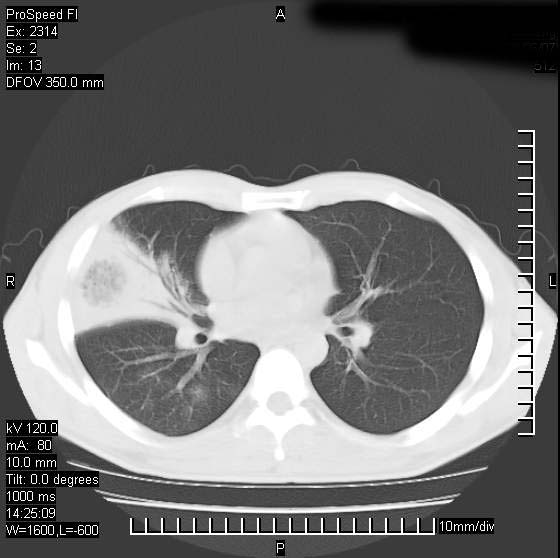

男性,再生障碍性贫血,入院前发热10天,最高40c,右侧胸痛,外院ct示右上,中肺边缘模糊的球性影(就是我现在图中标示的范围),考虑炎症,在我院使用头孢呋辛,洛美沙星10天,高烧消退,自感下午稍有发热,但今天ct示右上,中肺病灶明显扩大,还是考虑炎症,看其中的球型影是否霉菌感染??,是否能排除结核?

右肺中叶外侧段病变,上缘界限不清,下缘锐利,以段性发病为主,内见巨大空洞及空洞内容物,结合病史首先考虑:化脓性肺炎。不除外霉菌感染!

片状高密度影内见空洞影,内可见球形软组织密度影,并有新月征,考虑霉菌感染.

支持右肺上叶、中叶外侧段节段性肺炎伴脓肿形成。